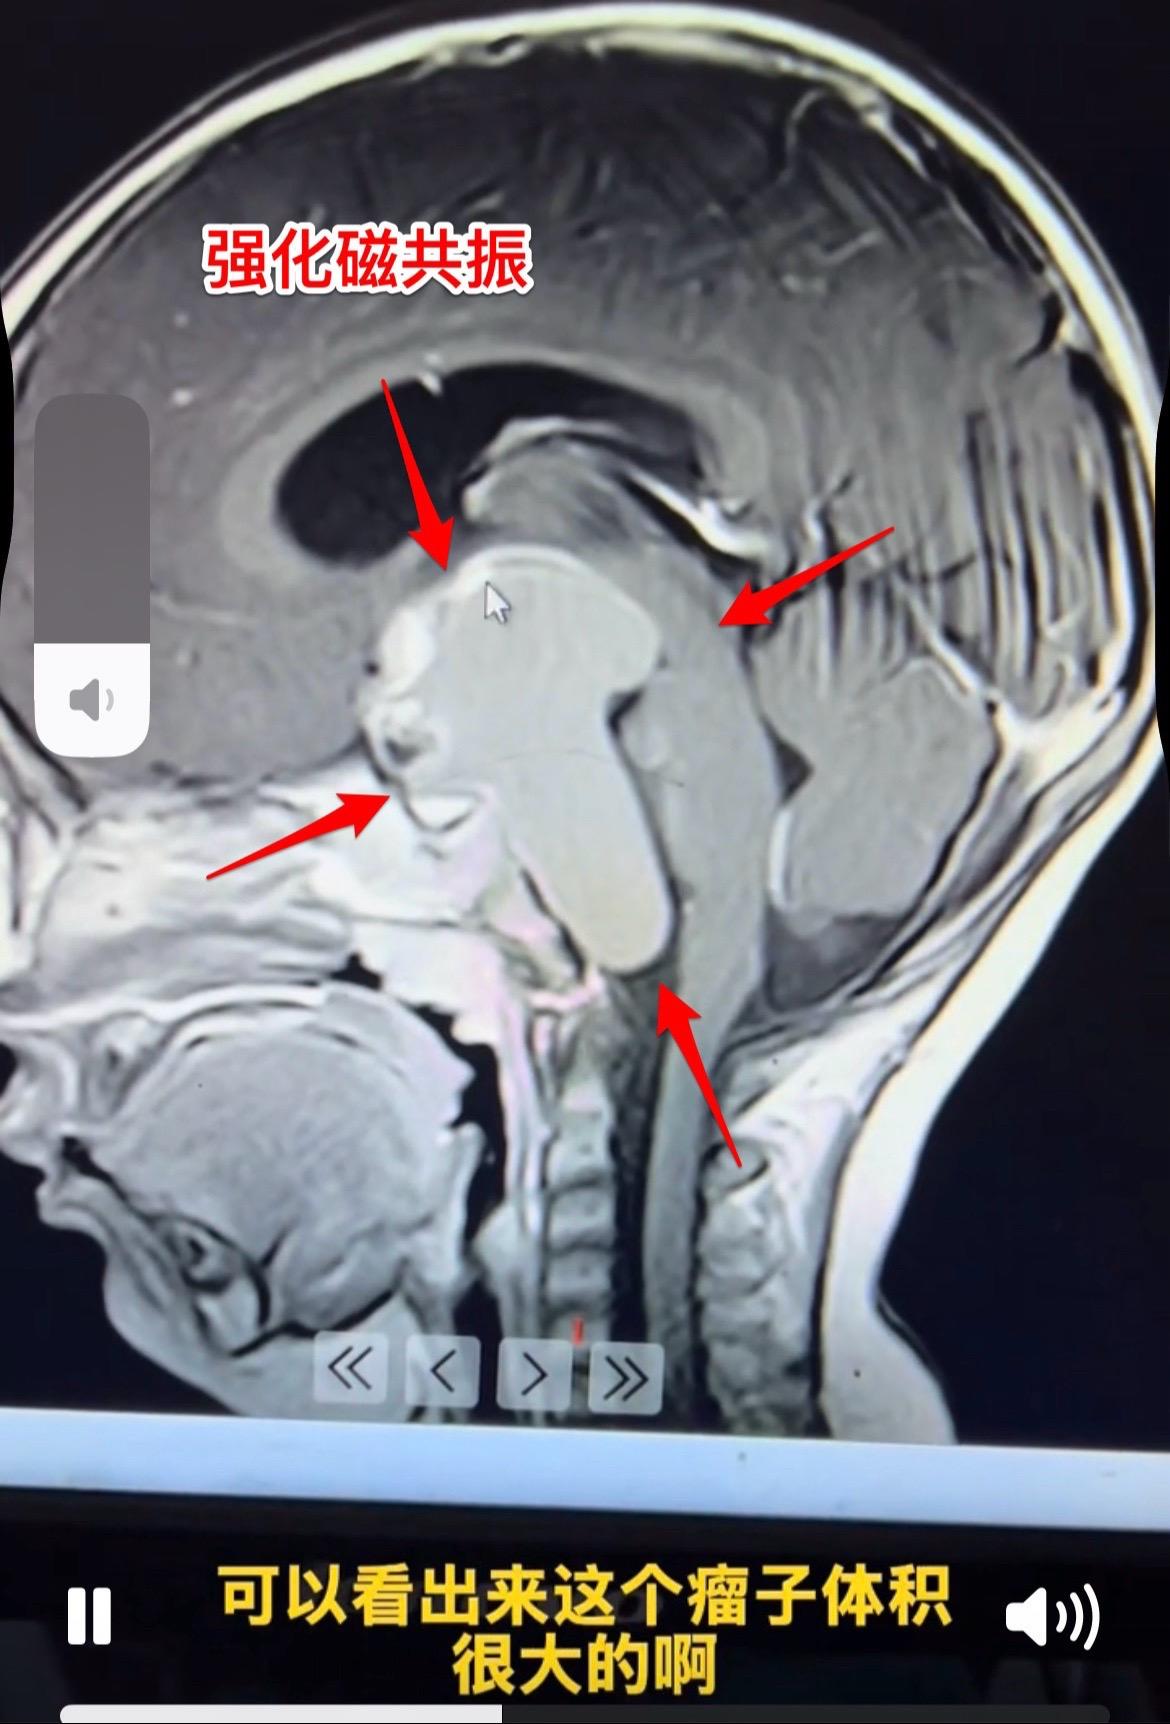

一岁十个月小孩子颅咽管瘤手术后11天。身体终于缓过来了! 现在她的精神状态好,能吃能喝,和家长交流也没有障碍,能看见手机视频。左侧眼睑下垂症状改善了,两个眼睛看起来是对称的。 由于颅咽管瘤体积大,刚刚做完手术时,小朋友身体很弱,出现贫血、低蛋白血症、电解质紊乱。有一次低钠血症还造成癫痫发作。 好事多磨!经过精心治疗和护理,小朋友熬过了一关又一关!近期有望出院了。颅咽管瘤眼睑下垂